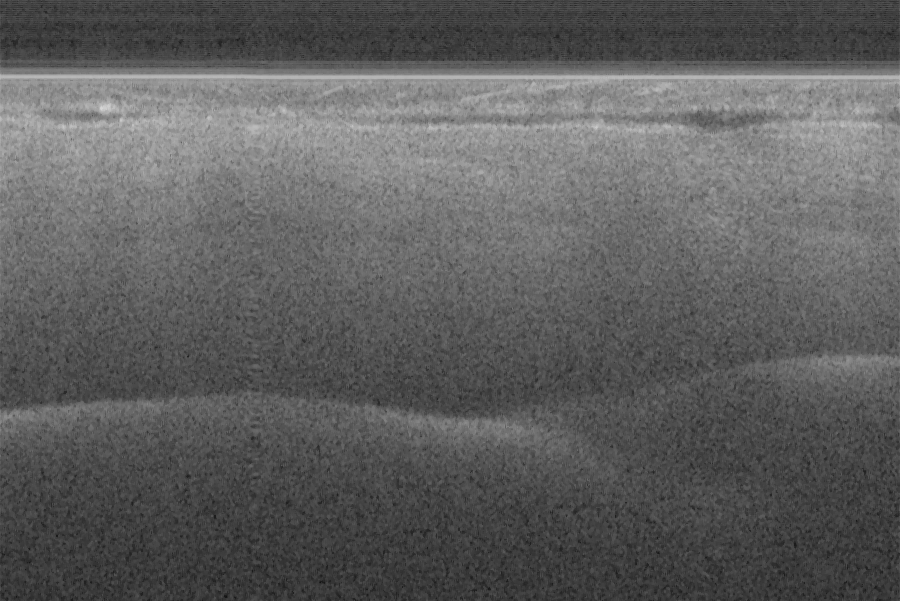

Fig. 16 (a) and (d) show SS-OCT images of human finger in vivo taken using fiber probes #

14 (working distance, depth of field and spot diameter of 1.2 mm 1.1 mm, and 27 m) and #

16 (working distance, depth of field and spot diameter of 0.9 mm 0.33 mm, and 16 m)

10

acquired by our catheter-based complex SS-OCT using our 3x3 Mach-Zehnder

interferometer with unbalanced differential detection technique with image size of 5x2mm.

The image depth shown in Fig. 16 (a) is slightly larger than that in Fig. 16 (b), but the image

is blurrier in Fig. 16 (a) than that in Fig. 16 (b), which taken by the probe with larger depth of

field and spot size. The image shown in Fig. 16 (b) has higher resolution than that in Fig. 16

(a), which can be seen clearly with finer structures in layer of epidermis (grey arrow), sweat

gland (white arrow), and blood vessel in subcutis layer (black arrow).

Fig. 16. In vivo human finger SS-OCT images taken with probe #14 (working distance, depth

of field and spot diameter of 1.2 mm 1.1 mm, and 27 m) and # 16 (working distance, depth

of field and spot diameter of 0.9 mm 0.33 mm, and 16 m) acquired by our catheter-based

complex SS-OCT using our 3x3 Mach-Zehnder interferometer with unbalanced differential

detection technique with image size of 5x2mm.